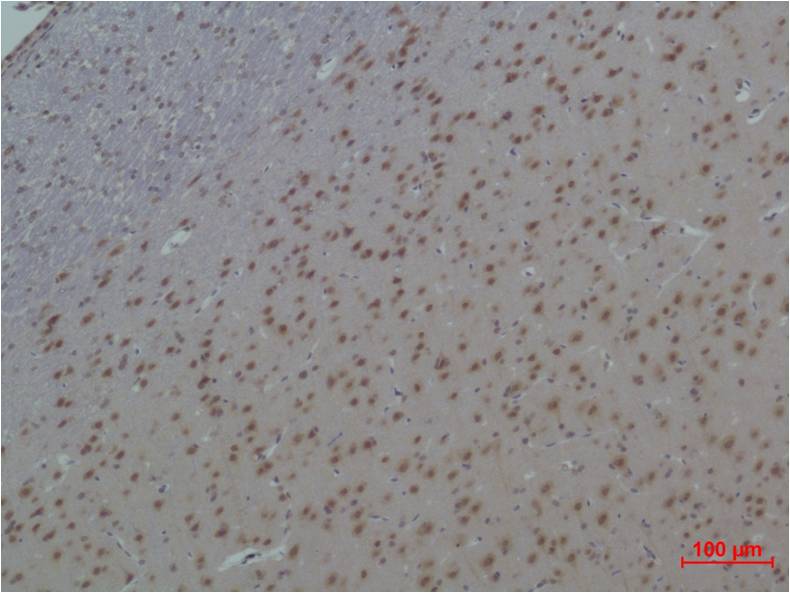

| Product name: | 14-3-3 epsilon Rabbit pAb |

| Dilutions: | WB 1:1,000 IHC 1:200-500 |

| Cellular localization: | Cytoplasm, Nucleus |